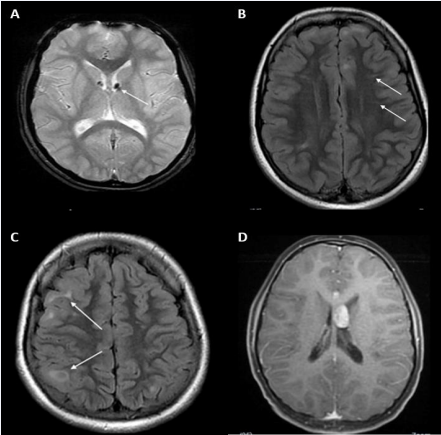

MRI records were available for 14 patients. Notably 10 of these 14 patients had more than 10 cortical tubers evident in their brain MRI scans, 3 patients had between 3 and 10 tubers, and 1 patient had less than 3 tubers. Representative examples of typical TSC-associated brain alterations from the present cohort are shown in Figure 1.

Figure 1 Brain MRI images from patients diagnosed with TSC showing characteristic features (arrows) of the disease. (A) SEN. (B) Radial migration lines. (C) Cortical tubers. (D) SEGA.